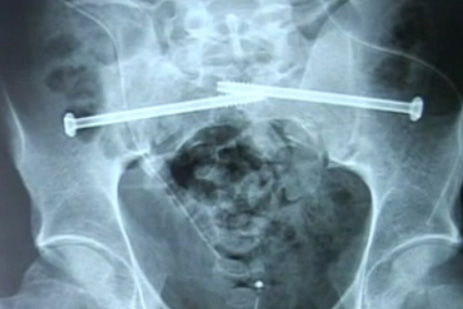

Mike Booth highsided his CBR600RR at Brands Hatch in the National Superstock 600 race and was hit by another rider. The crash broke Booth's pelvis and disconnected his spine from his pelvis, he has spent weeks in a wheelchair and undergone intensive surgery. His spine is now held in place with two bolts.